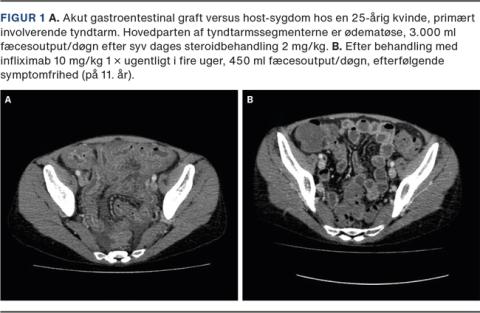

Akut GVHD opstår inden for de første tre måneder efter transplantationen, og oftest er huden involveret, dernæst gastrointestinalkanalen og leveren. På huden udvikles et makulopapuløst eksantem, der i alvorlige tilfælde kan gå over i toksisk epidermal nekrolyse [15]. Gastrointestinalkanalen kan blive svært påvirket med destruktion af epitel, hvilket kan føre til svære diarréer samt væske- og elektrolyttab (Figur 1). Akut GVHD behandles initialt med højdosissteroid, ved terapisvigt tillægges infliximab [16], ruxolitinib [17] eller ekstrakorporal fotoferese [18]. Akut GVHD medfører øget morbiditet og mortalitet i form af infektioner, medicinbivirkninger og organsvigt. Mismatchet donor, høj alder og intensiv konditionering bidrager til øget forekomst af GVHD, men også det fækale mikrobiom er indgået i kliniske studier gennem de seneste år [19]. Der er fundet en sammenhæng mellem et dysbiotisk fækalt mikrobiom med nedsat diversitet, antal genomer og incidensen af akut GVHD. Den kausale sammenhæng er dog ikke påvist endnu, men er et hastigt ekspanderende forskningsområde [20].

Billede